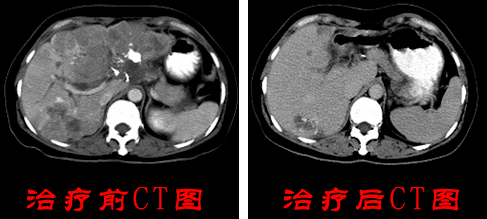

张某在我院接受3个疗程的WB-1无创全身热疗系统后,CT复查发现张某体内的肿瘤组织明显见好转,遂安排张某出院调养。